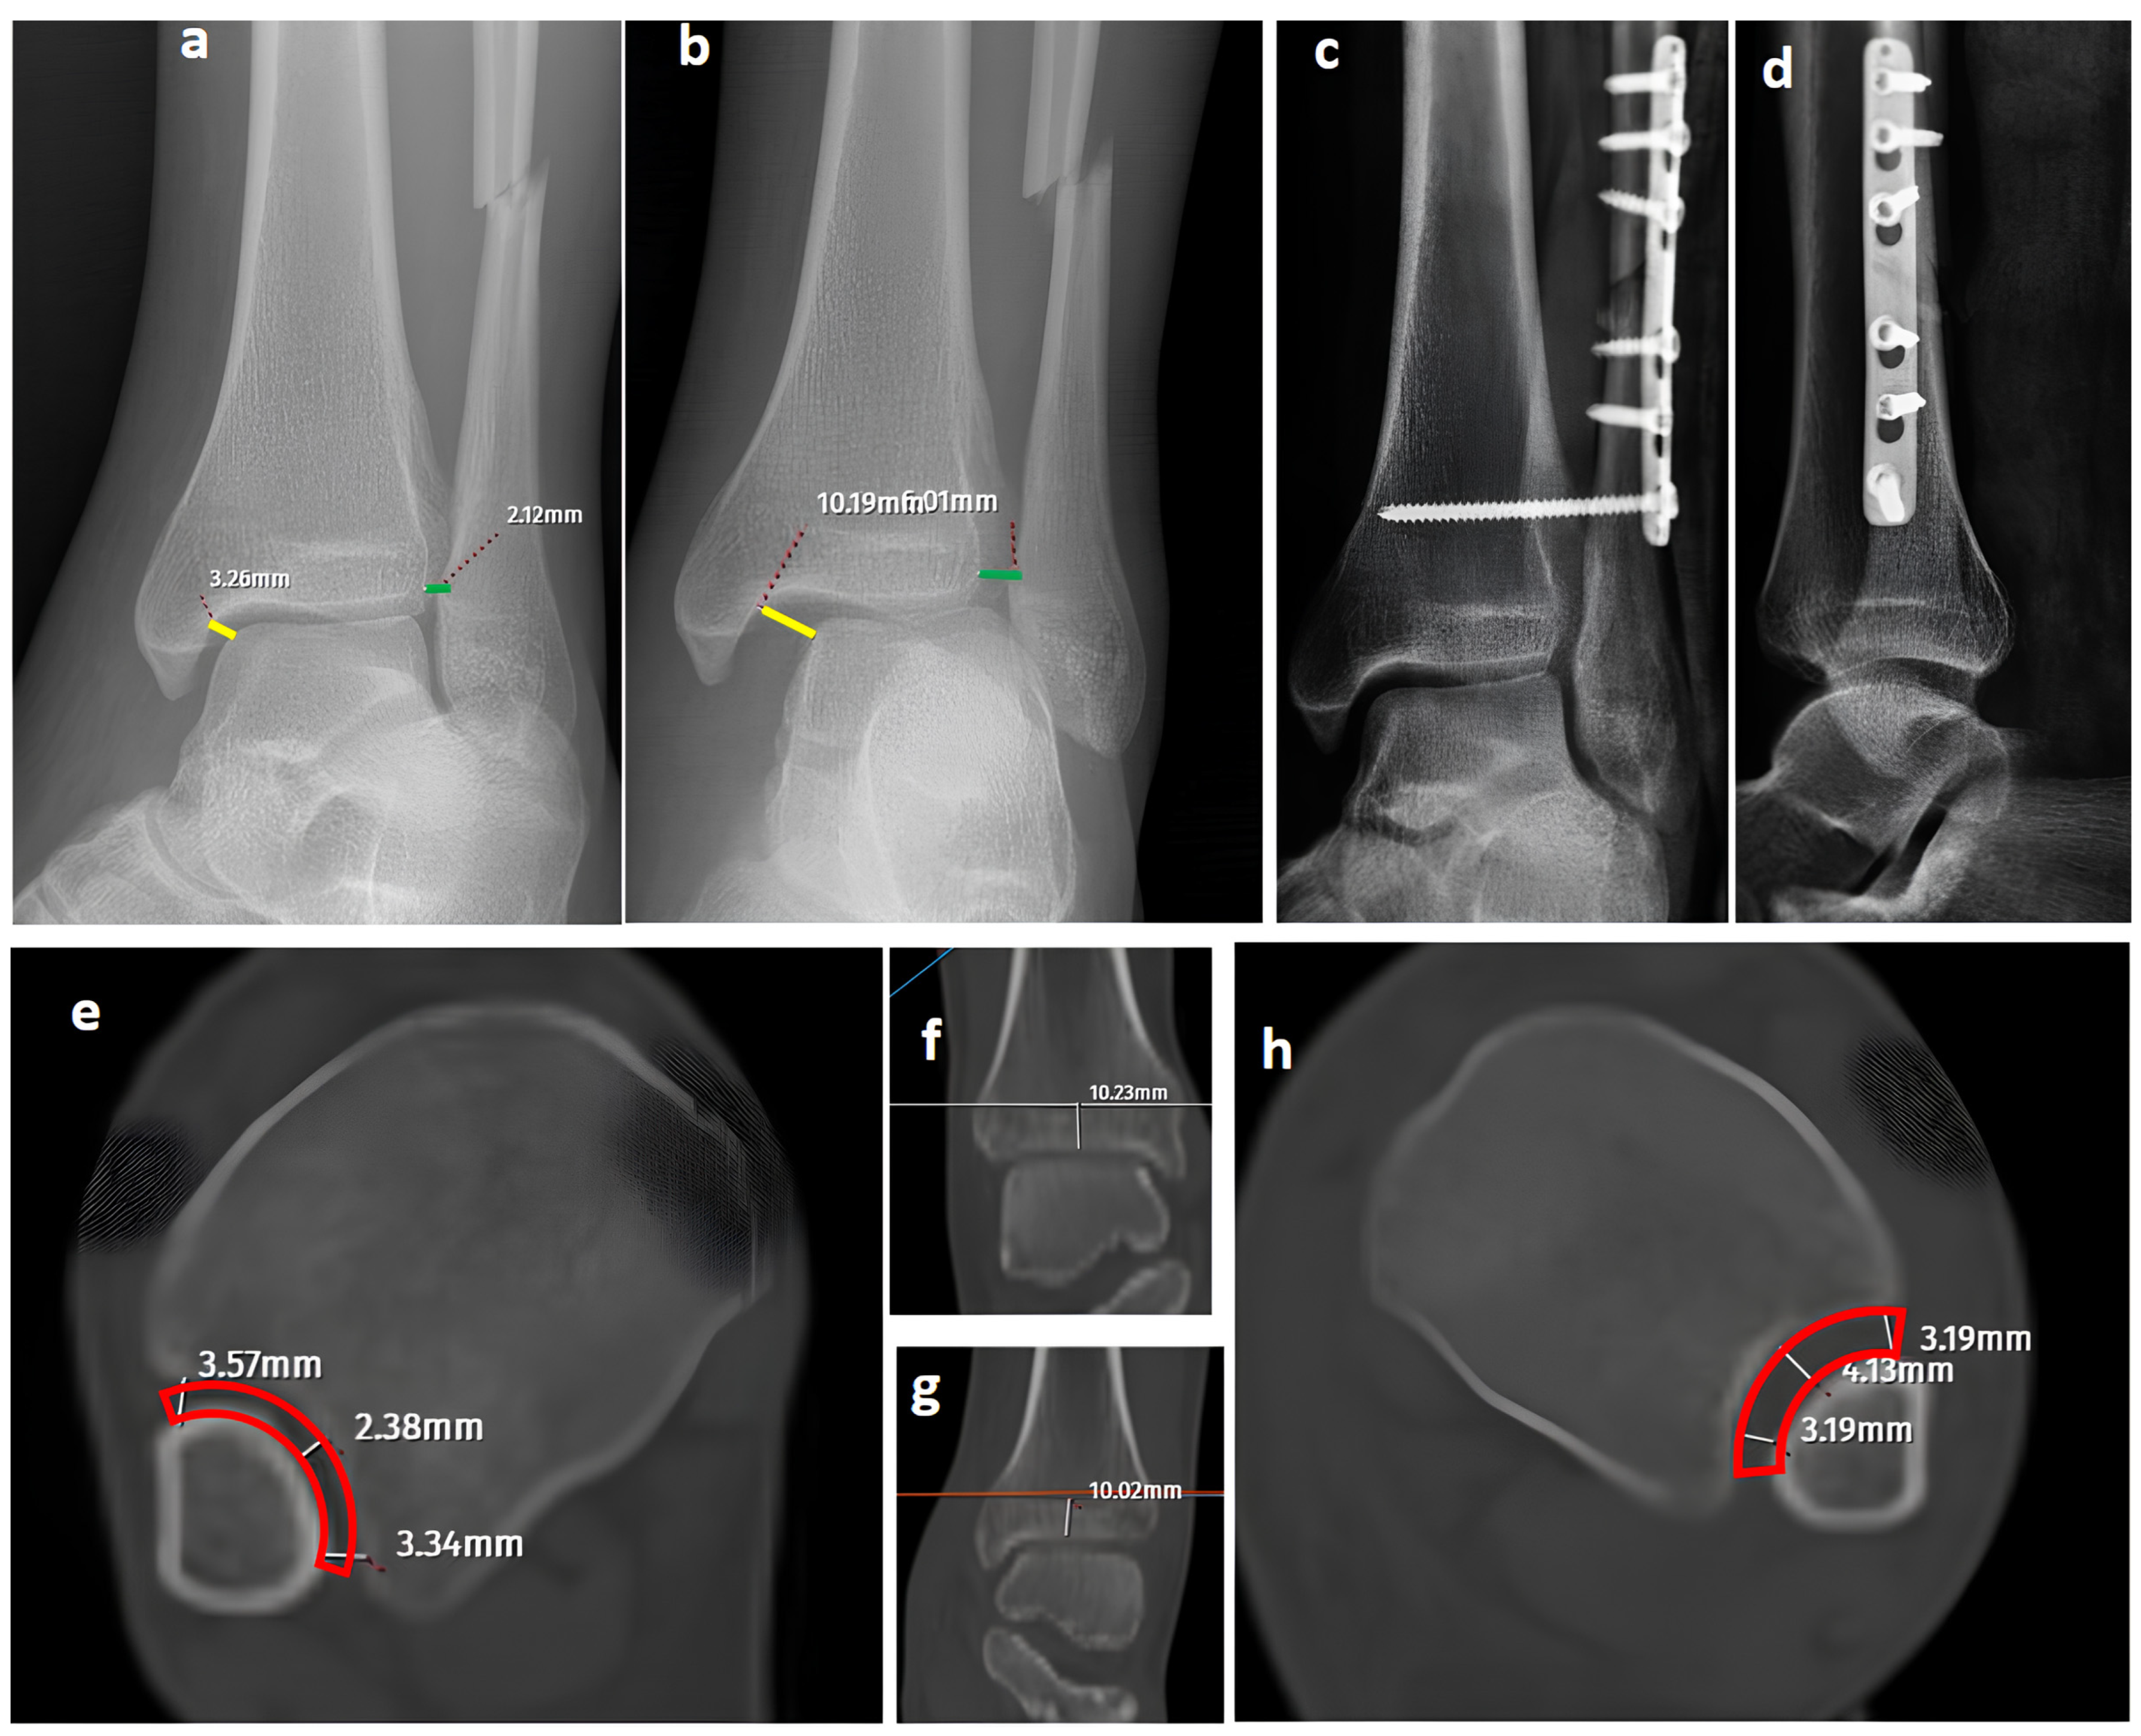

Figure 3.

A bimalleolar equivalent (pronation external rotation IV) left ankle fracture. (a) A mortise view showing a high lateral malleolar fracture with normal medial clear space (yellow line) and distal tibiofibular space (green line). (b) A GAASA image showing widened medial clear space (yellow line) and widened distal tibiofibular distance (green line), indicating syndesmosis injury and deltoid ligament injury concomitantly. (c,d) Initial postoperative AP and lateral X-rays showing anatomical reduction after fixation of the lateral malleolus and syndesmosis without repair of the deltoid ligament. (e–h) Axial CT images of both ankles. Although the left-side syndesmosis seems to be widened compared to the right foot, measurements are within normal ranges and do not indicate a syndesmosis injury (red block bows).

While axial CT images have provided reliable and specific assessments for syndesmosis injuries in previous studies, the diagnostic performance of CT was inferior to GAASA and mortise radiographs in this study [4]. Both inter-observer and intra-observer reliability revealed lower results compared to X-rays. This was an expected result, as the reliability of CT images is acceptable when volume measurement on axial images is performed at 10 mm over the plafond. In our study, the reason for evaluating the CT images subjectively without measurements was to mimic clinical practice scenarios where quantitative measurements are not always feasible. Relying solely on subjective evaluations of widening on axial CT images over the 10 mm plafond is potentially misleading. Even meticulous measurements on CT images do not guarantee accurate efficacy in detecting syndesmosis injuries. Yeung et al. [4] reported excellent inter-observer reliability for CT images in evaluating syndesmosis injuries. However, they found only a 56.4% sensitivity and 91.7% specificity on ROC curves, indicating the limitations of this approach. Despite excellent inter-observer reliability, the syndesmosis itself may not appear widened if unstressed or if any structures block the fibula from reducing to its proper position in CT imaging. When in a reduced position, the tibiofibular distance could appear within normal ranges on CT images and mortise radiographs (Figure 3) [1]. Researchers have proposed using direct arthroscopic visualization of the syndesmotic joint as a more precise diagnostic approach, as no imaging modality is perfect at detecting syndesmosis injuries [33]. From this perspective, some authors have utilized both conventional and dynamic ankle CT scans performed under forced external rotation, dorsiflexion, and axial loading in various foot positions. Their results revealed that applying stress significantly improves the diagnostic performance for detecting subtle syndesmotic instability [20,21]. To reduce radiation exposure and minimize the pain caused by stress applied to the ankle, ultrasonography (USG) has been utilized for the detection of ankle ligament injuries. It has been shown that ultrasound has good to excellent diagnostic value for complete discontinuity of the anterior talofibular ligament (ATFL) and the anterior inferior tibiofibular ligament (AITFL). Compared with static ultrasound, dynamic ultrasound demonstrated inferior diagnostic value for detecting complete discontinuity of the AITFL [34]. Although USG has high sensitivity and specificity in identifying ligamentous injuries such as the ATFL and AITFL, its role in assessing syndesmosis stability remains unclear. This is because the syndesmosis complex comprises five anatomical components, and in most cases, instability occurs only when all five structures are disrupted [31,35]. Furthermore, from an orthopedic surgeon’s perspective, the use of USG may not always be feasible or practical due to its operator-dependent nature, limited availability in some clinical settings, and the requirement for significant expertise to ensure accurate and reliable results.